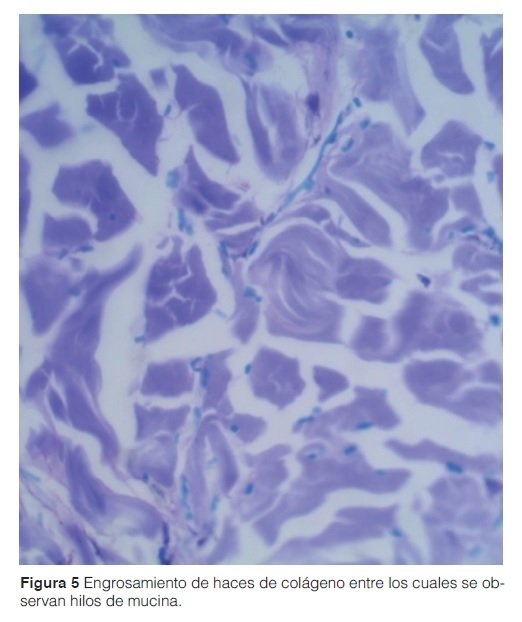

Estudios laboratoriales (hemograma, hepatograma, perfil tiroideo, ANA, anti DNA, anti-Scl 70, anticentrómero, hepatitis virales, proteinograma electroforético) resultaron normales. Las pruebas de función respiratoria revelaron un patrón restrictivo en la espirometría con una TACAR de tórax y una ecocardiografía normales. La anatomía patológica de la biopsia de piel reveló aumento del espesor de la dermis debido a la presencia de haces de colágeno ensanchados, esclerosis y leve infiltrado inflamatorio perivascular. Se observaron además hilos de mucina. Por este dato, junto con la clínica compatible se llegó al diagnóstico de Escleredema Adultorum de Buschke tipo dos. (Fig 5).

El diagnóstico del Escleredema de Buschke se basa en el cuadro clínico y en los hallazgos histopatológicos, que se destacan por presentar cambios mínimos en la epidermis con importante engrosamiento de la dermis por depósitos de colágeno de tipo I separados por depósitos de mucina, que se identifican con coloraciones especiales4.

A las Dras Di Martino y Pefaur por facilitar la imagen correspondiente a la anatomía patológica.